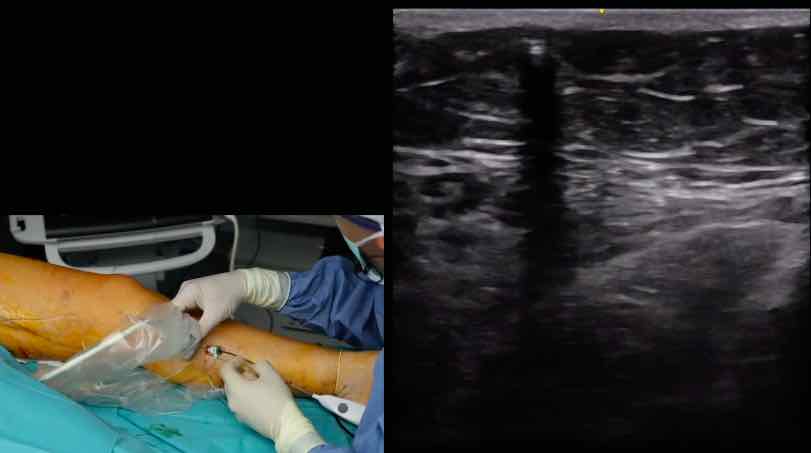

15. Freiburger Venen-Workshop – thumbnail 1 of 8 15. Freiburger Venen-Workshop – thumbnail 2 of 8 15. Freiburger Venen-Workshop – thumbnail 3 of 8 15. Freiburger Venen-Workshop – thumbnail 4 of 8 15. Freiburger Venen-Workshop – thumbnail 5 of 8 15. Freiburger Venen-Workshop – thumbnail 6 of 8 15. Freiburger Venen-Workshop – thumbnail 7 of 8 15. Freiburger Venen-Workshop – thumbnail 8 of 8

15. Freiburger Venen-Workshop

Live-Operationen - Endovenöse Technik sinnvoll einsetzen